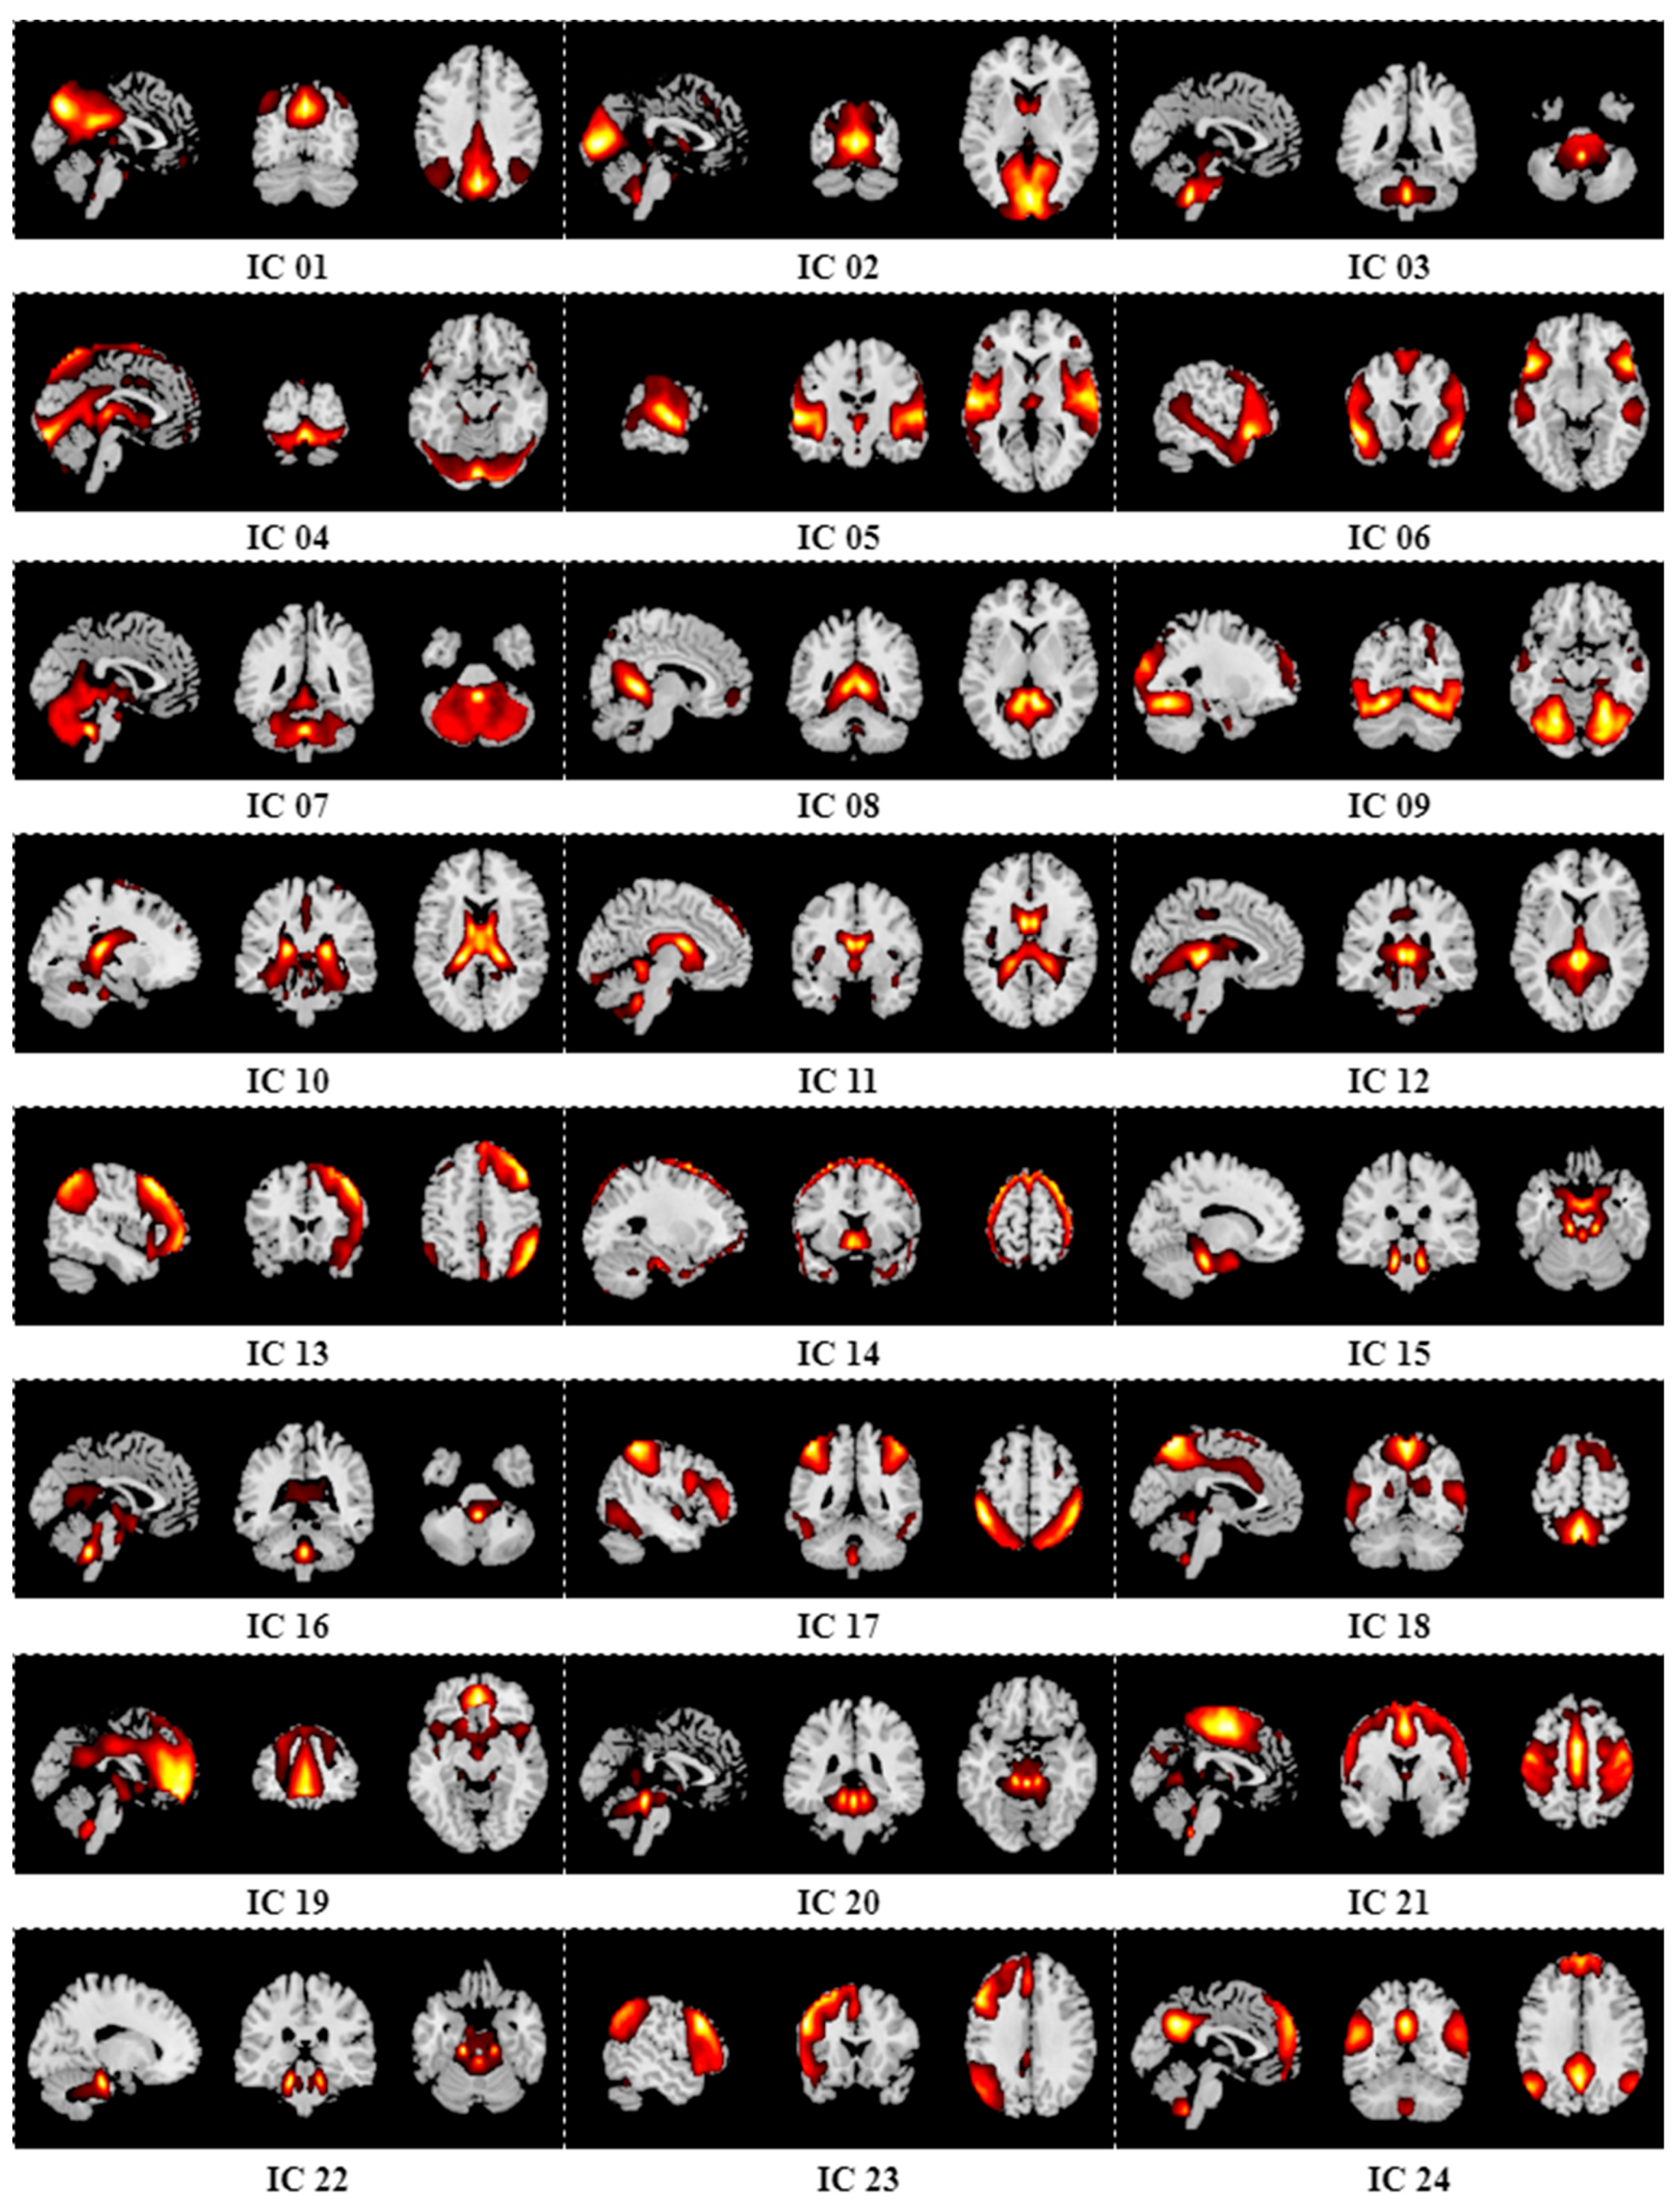

Appendix B. Results of Group ICA

| 27 | 69.52% | 81.15% | 73.71% | 66.61% |